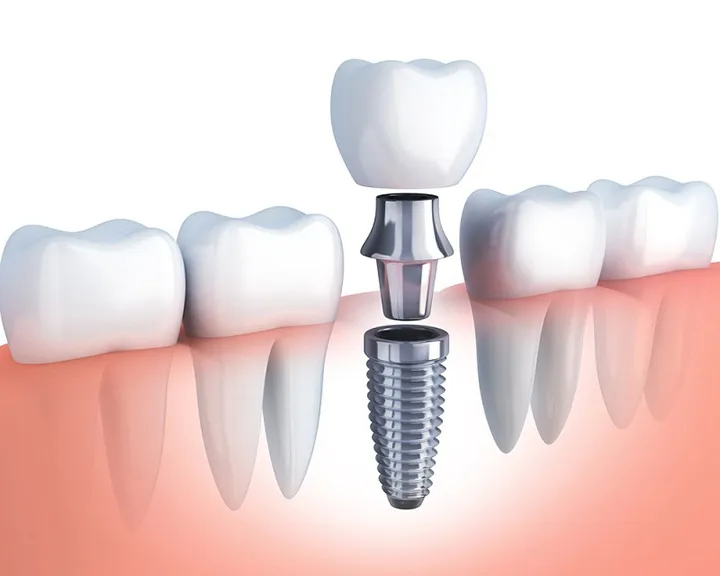

Bọc răng sứ là một phương pháp nha khoa thẩm mỹ nhằm phục hình răng bị tổn thương, răng kém thẩm mỹ. Không thể phủ nhận lợi ích của việc bọc răng sứ, tuy nhiên nó cũng gây ra tình trạng viêm chân răng bọc sứ. Nguyên nhân khiến bạn phải đối mặt với tình trạng này đó là.

Kích thước răng sứ sử dụng không tương thích

Răng sứ phải được sử dụng với kích thước phù hợp, răng sứ tương thích với kích của ổ răng và mô nướu của khách hàng. Trường hợp răng sứ bị vênh, hở, cộm… sẽ tạo khe hở để vi khuẩn xâm nhập. Sau một thời gian, làm răng sứ xong bị viêm lợi không phải điều hiếm gặp.

Bạn sẽ được thiết kế bộ răng sứ mới phù hợp hơn, ôm khít với nướu và ổ răng, không cho vi khuẩn xâm nhập. Lúc này, răng sứ cũ sẽ được tháo ra để thay vào bộ răng mới đẹp và phù hợp hơn.